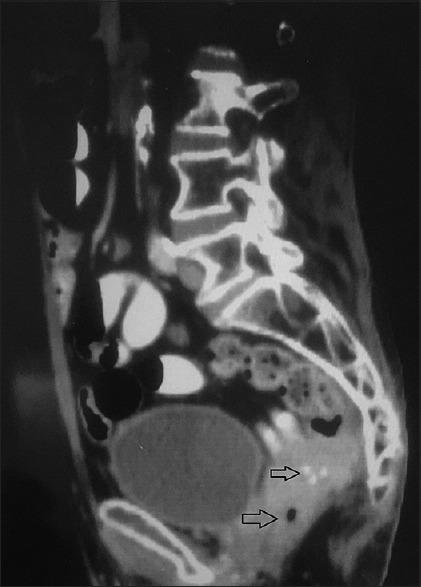

A total of 31 biopsy proven patients showing variable bowel wall thickening involving the colon /rectum on CECT (Contrast Enhanced Computed Tomography) were included in the study. The tumours were staged based on the CT scan findings and were compared with the operative and histopathological findings.

Rectum was the most common site of involvement followed by the recto-sigmoid involvement. Metastasis was observed in 5 cases out of the 31 malignant cases. Five of the 7 cases were correctly staged as T1 & T2 lesions on CT having a sensitivity of 83.3%, specificity of 92%, and positive predictive value of 71.4% and a negative predictive value of 95.8% in the diagnosis of T1 and T2 lesions. 15 of the 16 cases were correctly staged as T3 lesions. CT had a sensitivity of 88.2%, specificity of 93.8%, and positive predictive value of 93.8% and a negative predictive value of 86.7% in the diagnosis of T3 lesions. All the 8 cases were correctly staged as T4 lesions. CT had a sensitivity of 100%, specificity of 100%, and positive predictive value of 100% and a negative predictive value of 100% in the diagnosis of T4 lesions.

本研究纳入了31例经活检证实、在对比增强计算机断层扫描(CECT)上显示结肠/直肠肠壁增厚情况各异的患者。根据CT扫描结果对肿瘤进行分期,并与手术及组织病理学结果进行比较。

直肠是最常受累的部位,其次是直肠乙状结肠交界处受累。31例恶性病例中有5例出现转移。7例中的5例在CT上被正确分期为T1和T2病变,在诊断T1和T2病变时,敏感性为83.3%,特异性为92%,阳性预测值为71.4%,阴性预测值为95.8%。16例中的15例被正确分期为T3病变。CT在诊断T3病变时,敏感性为88.2%,特异性为93.8%,阳性预测值为93.8%,阴性预测值为86.7%。所有8例均被正确分期为T4病变。CT在诊断T4病变时,敏感性为100%,特异性为100%,阳性预测值为100%,阴性预测值为100%。